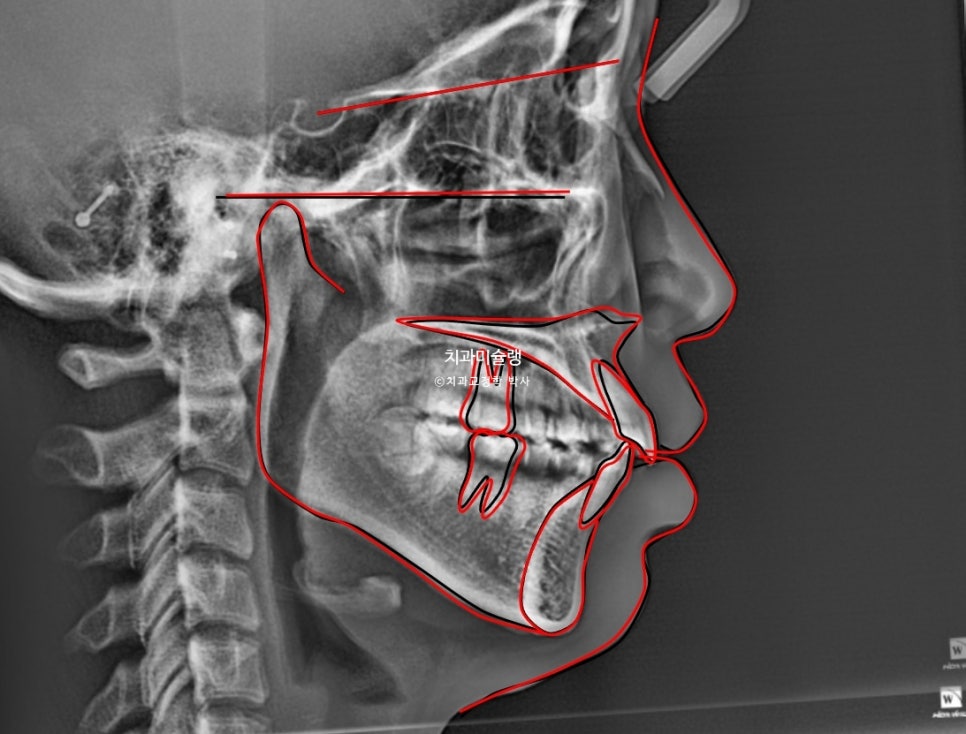

본원에 과거 4월 교정 전 엑스레이 자료가 있어 현재 11월 상태와 객관적으로 중첩을 해보았습니다.

까만선이 24년 4월 초진, 빨간선이 24년 11월 입니다. 2급 고무줄을 끼면서 위 앞니와 어금니를 포함한 전체치열이 뒤로 소량 들어가고 아래 전체치열은 앞으로 소량 나온것이 확인됩니다.

과개교합이라도 먼저 해결을 한 후 2급 고무줄을 꼈다면 모를까, 과개교합 개선이 안된 상태에서 이러한 치아이동은 앞니에 더 심한 교합간섭을 만들고 다물때 아래턱이 뒤로 밀리는 증상이 생길 수 밖에 없죠. 아래턱이 뒤로 밀리면 관절공간을 압박하여 턱관절 통증이 생길 수 있습니다.

교정 전후 옆 엑스레이 중첩입니다. 앞니 돌출이 해소되며 입술이 한결 편하게 다물립니다. 뒤로 밀렸던 턱이 과개교합이 해소되면서 소량 앞으로 나왔습니다.